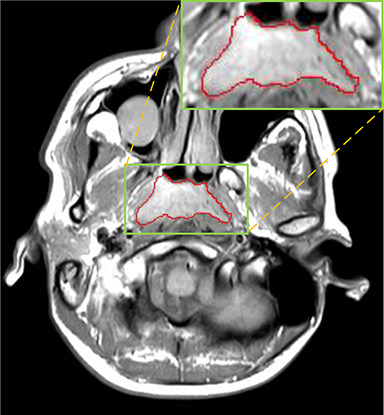

Currently, there is still no effort to fuse multi-modality MRI to develop an automatic segmentation system for NPC. According to researches of Popovtzer et al. [16], it should be a routine clinical practice to incorporate all kinds of MRI datasets in highly conformal radiation therapy to realize GTV delineation of NPC. For delineation of NPC, MRI is the perferred imaging modality for its superior soft tissue contrast [16, 3]. Moreover, MRI of different modalities data have different visual characteristics and various responses to different tissues and anatomical structures. For example, T1-weighted (T1) MRI is suitable for detecting skull base involvement and fat planes, while contrast-enhanced T1-weighted (CET1) MRI is used to identity tumor extent [3]. Figure 1 shows some examples of NPC response in T1, CET1 and T2-weighted (T2) MRI.

Comparison with ground truth. Some predicted results of MMFNet are shown in 2D images and 3D images in Figure 7 and Figure 8. As shown in these figures, although the shape and size of NPC are varied from each other, MMFNet can still accurately determine the regions of NPC and obtain the accurate contours of tumors. Through analyzing 2D images in figure 7, MMFNet has a capacity to fuse multi-modality MRI to reduce the confusion brought by intensity’ similarity between nearby tissues and NPC. The values of , and of MMFNet are shown in Table 1. MMFNet can reach the best results with , and .